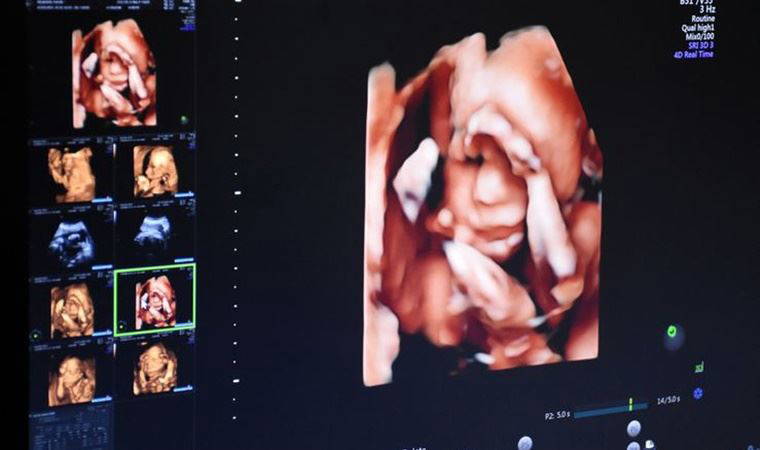

Ayrıntılı ultrason taramasının teknik açıdan standart ultrasondan herhangi bir farkı bulunmadığını belirten Uzm. Dr. Ferda Ağırgün, “Standart ultrasonda bebeğin genel sağlık durumu incelenirken ayrıntılı ultrasonda her organ tek tek incelenir. Yani daha detaylı görüntüleme söz konusudur ancak kullanılan tüm yöntemler standart ultrasonla aynıdır. Organların ayrı ayrı incelenmesi ise pek çok durumun daha net görülmesini sağlar. Örneğin bebeğin beyni, böbrekleri, iç organları veya kemikleri düzgün gelişmemiş olabilir. Bazı bebeklerin omuriliği etkileyen ve açık spina bifida adı verilen bir sağlık sorunu olabilir. Bu soruna sahip her 10 bebekten 9’u genellikle ayrıntılı taramada tanı alır. Aynı durum yarık dudak olarak adlandırılan ağız yapısındaki bozukluk için de geçerlidir. Buna karşın kalp kusurları sorunlarının tespiti daha zordur. Kalp kusuru olan bebeklerin ise neredeyse yarısı ayrıntılı ultrasonda tanı alır” diye konuştu.